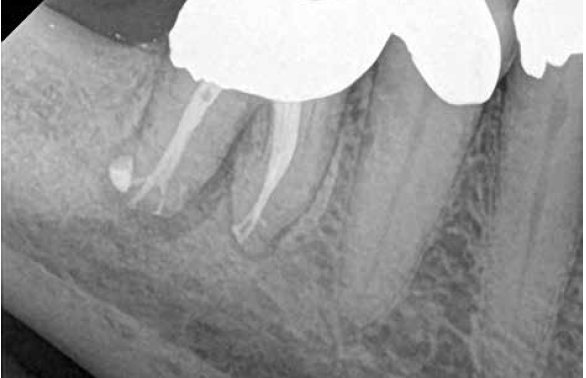

A body of research has emerged in recent years on the management of severe dental pain, exemplified by the diagnosis of an acute apical abscess where drainage cannot be achieved, symptomatic apical periodontitis, or irreversible pulpitis.11 An example of an acute apical abscess is depicted in Figure 1 and Figure 2. These conditions typically represent the most severe discomfort experienced by patients, and consequently, they serve as an excellent model for pain management. Treatment strategies for these issues and other painful conditions should include both definitive treatments for the diagnosed condition as well as adjunctive pharmacologic management.

(2.) The infection was managed with oral antibiotics, root canal therapy, and a combination of ibuprofen and acetaminophen to manage the preoperative and postoperative discomfort.

Figure 2